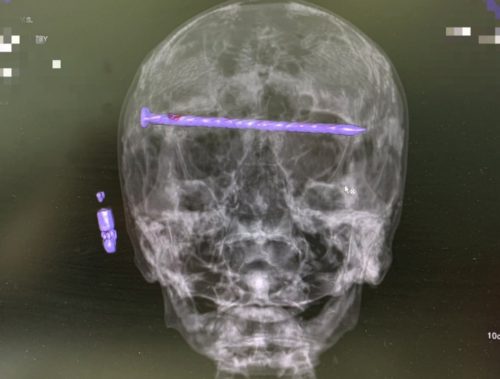

78-летнему пациенту извлекли 15-сантиметровый гвоздь из головы.

Нижнетагильские врачи в результате сложнейшей операции достали из головы 78-летнего пациента 15-сантиметровый гвоздь.

Мужчина поступил в приёмный покой Городской больницы №1 Нижнего Тагила в тяжёлом состоянии. На КТ медики увидели в костях черепа гвоздь, который прошёл через обе глазницы от правого до левого виска. Длина его достигала 15 сантиметров. Ситуация осложнялась повреждением твёрдой оболочки мозга и сдавлением глазных яблок.

Чтобы спасти пациента, бригада специалистов во главе с заведующим нейрохирургическим отделением ГБ №1 Нижнего Тагила Дмитрием Неволиным провела экстренную операцию. Гвоздь извлекли, сохранив мужчине и жизнь, и зрение.

Прооперированный мужчина под наблюдением бригады врачей быстро восстанавливается. Для профилактики осложнений он проходит антибактериальную терапию.